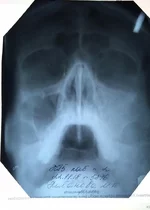

Вот решила к другому сходить врачу(в той же поликлиннике), он сделал снимок,увидел в носу какие то искривления, бугорок, говорит ей гайморит , надо пробивать чистить и т.д.. Вот тут Я совсем не понял, как врачи наши лечат(один одно,другой другое), решил проконсультироваться немного. Что нам делать и как поступить?

снимок прикрепил, скажите по нем видно чтото?

Забыл, есть старое еще фото 2010года( прикрепил)